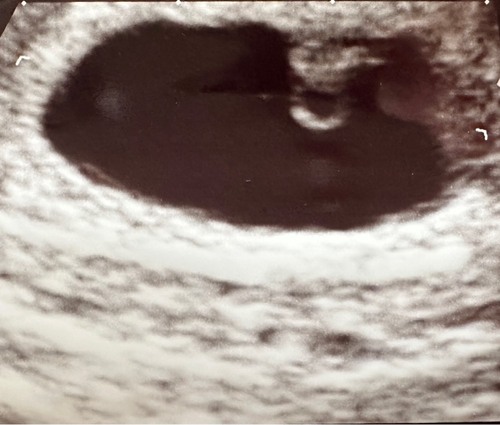

Mijn echo gisteren, uitwendig. Heeft iemand een idee wat het witte stipje bij baby B is? Bij baby A zag ik dit niet. Het viel mij net pas op. Dit is trouwens een uitwendige echo. Baby B is 7w2d op deze echo. En baby a 7w3d. Vandaag weer een dagje verder natuurlijk:)

En baby a beter in zicht.